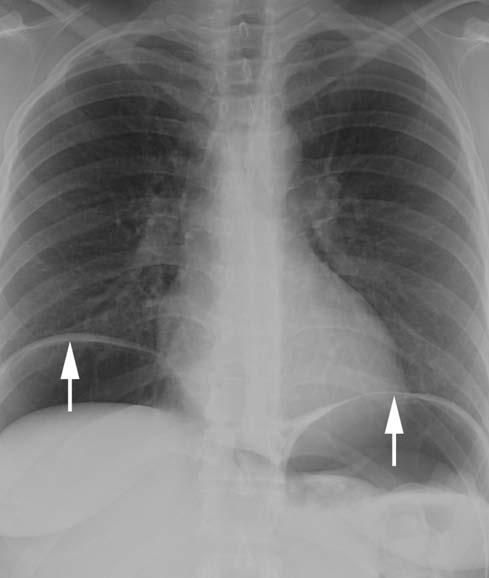

The patient's CT scan of the chest demonstrated small collections of gas in the mediastinum, consistent with pneumomediastinum (Figure 1). The chest radiograph showed a large amount of free air below both hemidiaphragms (Figure 2). Cardiac and mediastinal contours were within normal limits. The lungs were clear, and there was no pleural effusion.

Figure 2 – A large amount of free air under the diaphragm (arrows) can be seen in this portable chest radiograph obtained in the emergency department.

Thus, the assessment of a patient with pneumomediastinum should include a careful consideration of both intrathoracic and extrathoracic causes. In this case, the subsequent development of a large amount of free intraperitoneal air on the chest radiograph raises concern for a perforated abdominal viscus as the most likely cause.